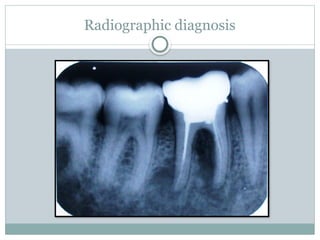

Radiographic diagnosis

Glickman (1958)

Grade-I:

 Incipient or early stage of furcation involvement.

 Pocket is suprabony

 Radiographic changes are not usually found

Grade-II:

 can affect one or more of the furcation

of the same tooth

 Lesion is essentially a cul-de-sac, with

definite horizontal component

 Radiograph may or may not depict the

furcation involvement